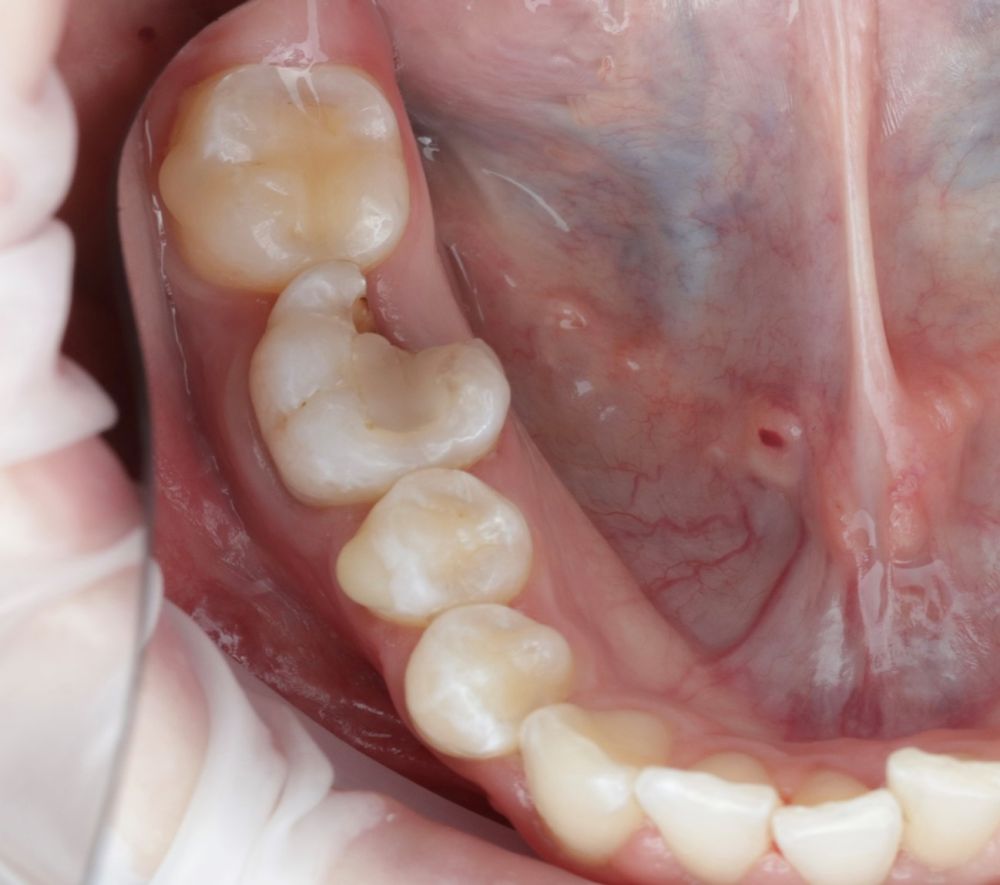

Se reporta el caso de un autotrasplante del tercer molar inferior derecho al alveolo postextracción de un primer molar inferior, en una paciente de 22 años de edad. Actualmente, el autotransplante se considera una opción de tratamiento si se siguen los criterios de selección del caso adecuados, y se realiza una técnica quirúrgica protocolizada. El diagnóstico planificado mediante CBCT, la simulación virtual y la confección de una réplica en 3D optimiza la técnica de forma segura, predecible con tiempos de cirugía menores.

Los dientes utilizados para realizar un AD más frecuentemente suelen ser de premolares a incisivo, de cordal a primer o segundo en pacientes jóvenes con ápice abierto. En adultos con ápice cerrado suele ser el autotransplante de cordal a primer o segundo molar3,4,6.

El diente donante ideal debería tener una anatomía radicular de fácil instrumentación endodóntica, y ápice abierto de al menos 1,5mm de diámetro para permitir una adecuada revascularización, con formación radicular de al menos 2/3. Así mismo, debería ser lo suficientemente pequeño para el asentamiento adecuado en el alveolo receptor, cónico, cuya extracción se pueda realizar de forma atraumática3,5,7.